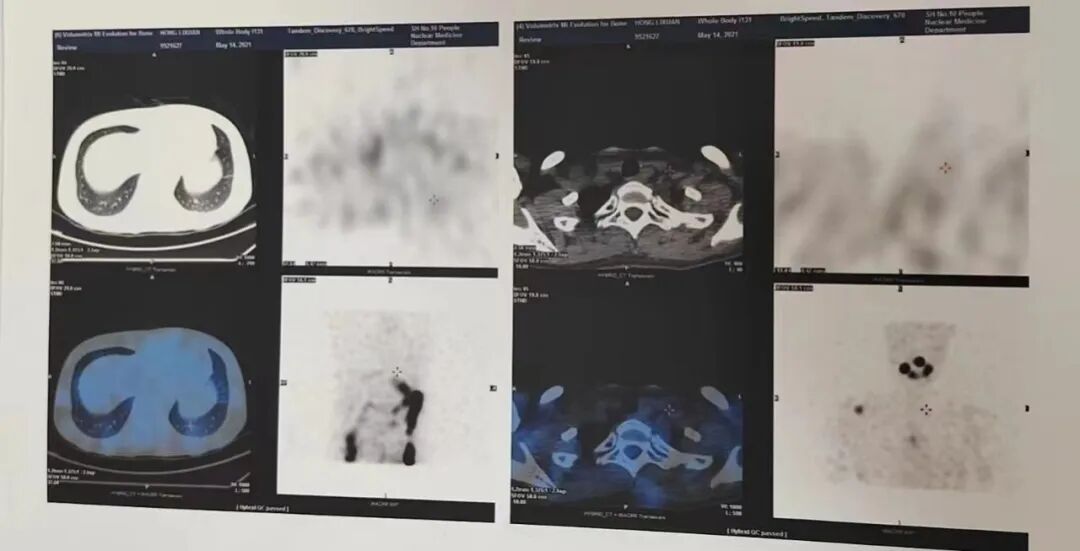

2019-04-09  PET-CT显像

病史及检查目的:

患者于2017-01-06日在我院行“甲状腺癌根治术+左叶全切+右叶近全切+中央区淋巴结清扫+喉返神经探查术”。病理结果:(左叶)甲状腺乳头状癌。(右叶)滤泡性肿瘤,恶性潜能未定,左侧中央淋巴结、右侧中央淋巴结转移。2017.04.10日碘131全身扫描:

1.甲状腺术后,残余甲状腺摄碘。

2.右侧顶骨、右侧肩胛骨关节盂、T11椎体、右则髂骨摄碘,全身多发骨转移。

3.双肺多发摄碘灶,肺转移。现拟行PET/CT.

诊断意见:

“甲状腺Ca根治术”后,术区未见明显异常放射性摄取增高影:双侧颈部IV区多个淋巴结,未见异常放射性摄取增高,转移不排除;左肺上叶尖后段、右肺下叶前、外基底段多发结节,未见异常放射性摄取增高,结合病史,考虑转移瘤肿瘤活性受抑制:右侧肩胛骨、T11椎体、右侧髂骨及左侧股骨上段多发溶骨性骨质破坏,右侧第5肋局部密度增高,部分病灶FDG轻度代谢增高,符合多发骨转移瘤表现,提示部分病灶仍存在肿瘤活性。

右侧上颌窦慢性炎症:双侧鼻咽部和扁桃体炎症;双侧颈部I、II区慢性炎性淋巴结可能性大。

胸腺退化不全;左肺下叶后基底段慢性炎性结节;少量心包积液;双侧少量胸腔积液;左侧斜裂胸膜钙化灶。

肝脏右叶良性病变(囊肿或血管瘤可能);左肾血管平滑肌脂肪瘤:右肾钙化灶;右肾旋转不良。

子宫腔内片状代谢增高:双侧附件区囊实性密度影伴代谢不均匀增高;盆腔少量积液;以上考虑与生理周期有关,请结合临床。

脑FDG代谢未见明显异常:右侧颅骨术后改变。